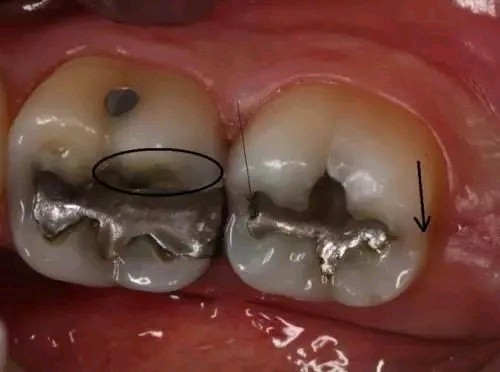

2 冰毒牙的症状

牙隐裂—冰毒会使服用者感到焦虑、亢奋或紧张,从而导致磨牙。你能看到他们的牙齿上有明显的磨耗痕迹。有时候就算是吃一些很软的食物(如土豆泥),也会使服用者的牙齿出现隐裂。

龋齿—冰毒成瘾者会因为口干反应而渴望吃含糖量高的食物和饮品。这样,口腔内靠糖类为生的细菌会大量繁殖,并分泌酸性物质,使牙齿损坏更严重。冰毒服用者的龋齿通常会从牙龈边缘发展到整个牙齿,前牙首当其冲。

冰毒牙的第一阶段:出现龋齿,口臭,牙龈红肿

冰毒牙的第二阶段:嘴唇上出现伤口,牙龈开始退缩,龋齿呈严重趋势

冰毒牙的第三阶段:龋齿发展到牙龈边缘以下,牙齿出现缺失,嘴唇的伤口越发明显